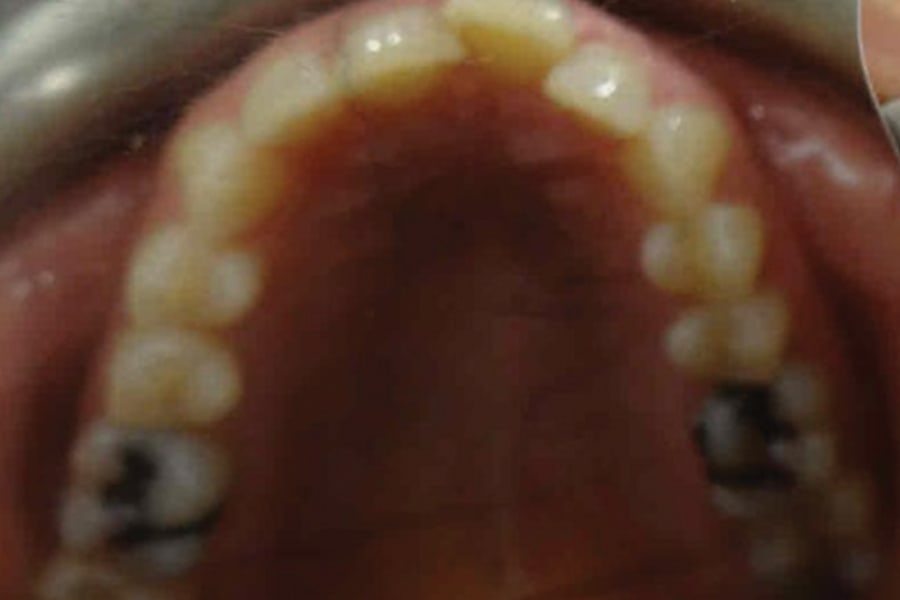

A 54-year-old woman presented with a chief complaint of teeth crowding. After comprehensive digital records were obtained, ClearCorrect® aligner therapy (Straumann, clearcorrect.com) was chosen with an anticipated 12-month treatment duration. The patient exhibited moderate anterior crowding, a class II molar relationship, and narrow arches. The treatment plan aimed to resolve the class II discrepancy, expand the arches, and establish proper anterior alignment. A total of 25 active aligners plus two retention aligners were prescribed. Attachments were selectively placed on the maxillary and mandibular canines to premolars, minimizing bulk while maintaining control over torque and posterior alignment. The patient was instructed to wear class II elastics full-time, which was crucial to achieving molar correction and arch expansion. Her outstanding compliance with class II elastics contributed to a significant improvement in molar position and transverse arch development. After completing the active phase, the patient transitioned to retainers to ensure long-term stability of the results. Given the patient’s initial class II occlusion, monitoring retention was emphasized to prevent relapse. The patient was extremely pleased with the outcome, demonstrating a broadened smile and improved occlusal function. This case underscores the effectiveness of ClearCorrect’s aligners in adult patients, particularly when combined with compliant elastic wear and targeted expansion strategies.